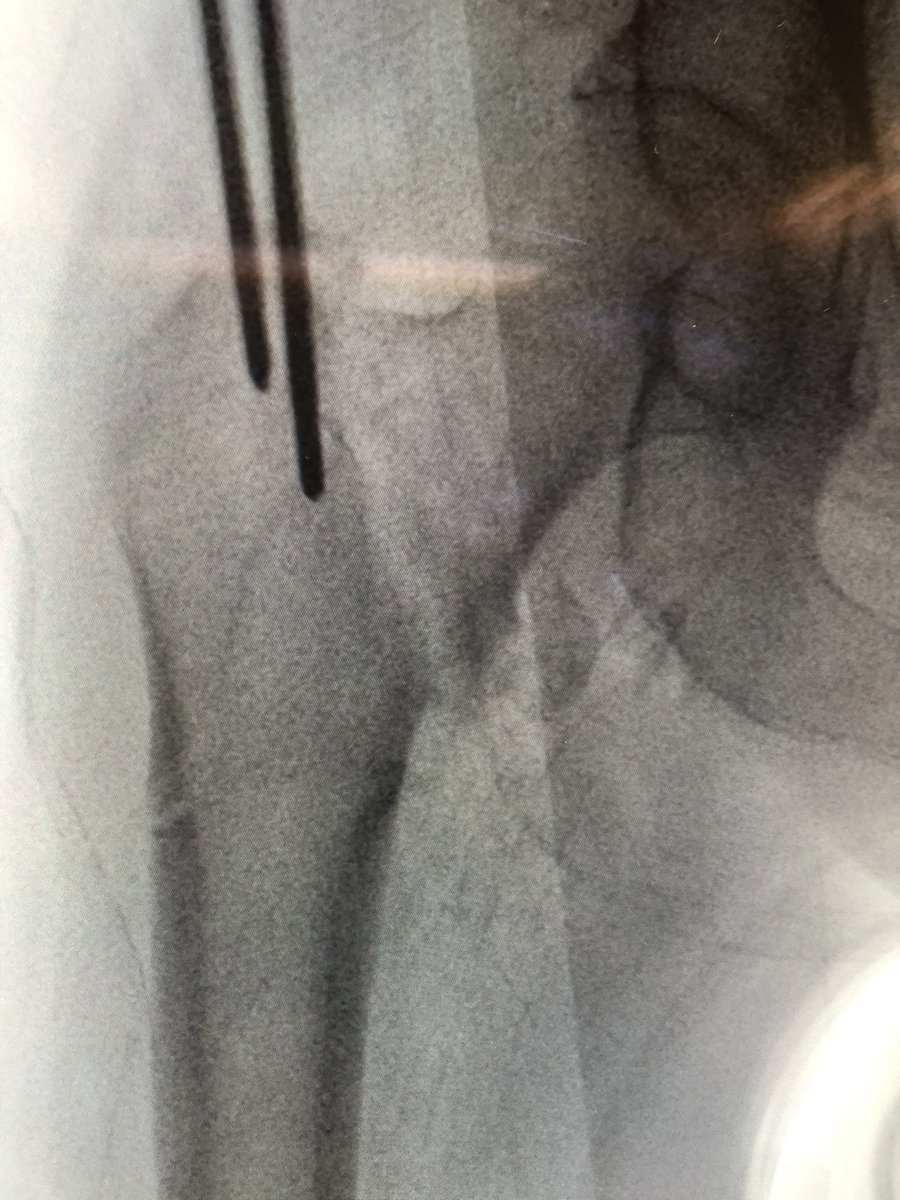

[11/18] I bring wire up to about blue level (I also like to stay inferior, yellow) in order to see it on lateral. Be sure to remove impactor (metal) otherwise will get in way of visual. If I need to change adjustment on lateral, I drill in reverse & redirect wire also in reverse.

[12/18] To see head well, the c-arm has to be sufficiently “wagged” proximally (yellow). Usually that solves most of my problems with lateral. My angle is about 75 deg from vertical in the other plane, to make up for the usual 15 degrees of anteversion (not quite a full lateral).

[15/18] I always try to build in some compression. The place to watch is the inferior medial portion of the fracture (arrow). Don’t overdo it or the nail starts to migrate medially.